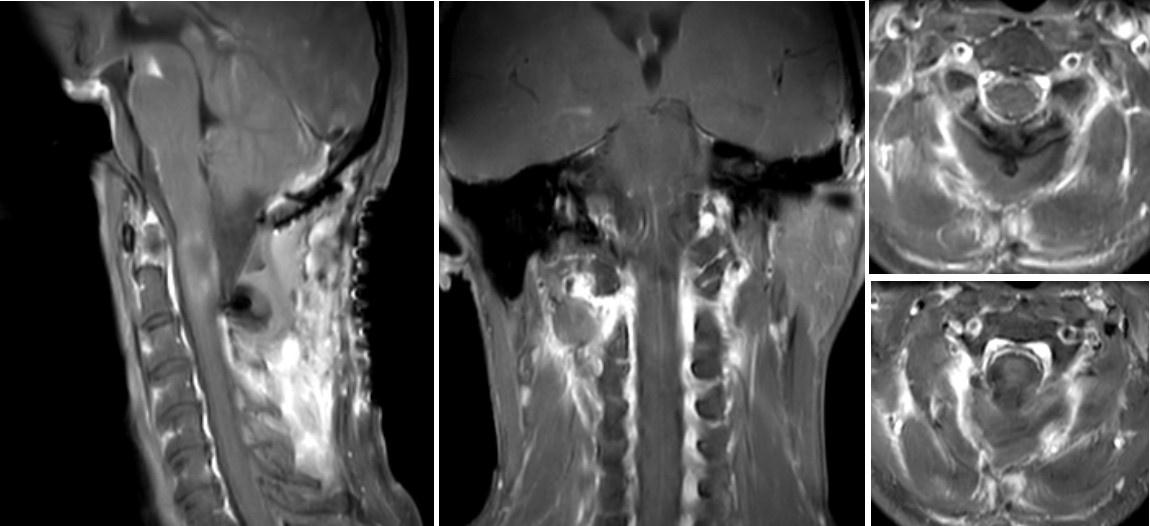

图2  张先生2016年(左)和2020年(右)核磁图像,提示肿瘤明显增大

图3 张先生在我院复查的核磁,病变范围从延髓到颈3椎体上缘

据王贵怀主任介绍,张先生罹患的是一种脊髓髓内肿瘤,很多病人长时间都没有明确症状,有些人会有“颈椎病”类似的表现。从患者目前的影像检查和病史来判读,考虑是室管膜瘤,它是脊髓常见的髓内肿瘤,这种病药物无法治愈,只能通过手术治疗,如果能够做到全切,术中对正常神经充分保护的话,病人将开启下一段正常的人生。但是肿瘤位置特殊,长在延髓到颈3椎体水平的脊髓内,手术需要切开脊髓进行,稍有不慎就会导致病人瘫痪,甚至呼吸心跳骤停,手术风险和难度极大。